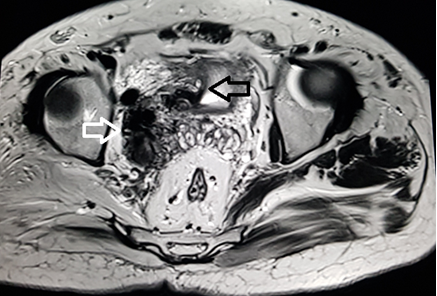

A 39 year old male presented with the chief complaint of pelvic discomfort and on and off haematuria. It was not associated with fever or urinary retention. No bowel symptoms were noted. Patient had history of paralytic poliomyelitis in his childhood and walked with crutches. On laboratory examination, patient was found to have deranged renal function tests with elevated creatinine level. Hence, we conducted MRI pelvis with MR urography to look for the urinary systemand to look for the status of the the pelvic muscles and joints. MR study showed multiple tortuous dilated vessels on the right side of pelvis suggestive of pelvic arteriovenous malformation (Figure 1&2). The arterial supply was noted from multiple branches of the right internal iliac artery and venous drainage was noted into right external iliac vein and deep external pudendal vein. The tangle of vessels was abutting the right lateral wall of urinary bladder, prostate and right seminal vesicle medially (Figure 1&3). It was abutting the obturatorinternus muscle laterally. There wasasymmetric thickening of the right lateral wall of urinary bladder adjacent to the vascular malformation (Figure 1). It was not associated with perivesicular fat strandings or enlarged locoregional lymphnodes. No restriction of diffusion was noted in DWI images. Prostate and bilateral bilateral seminal vesicles were normal in signal intensity and morphology. As a sequalae of childhood poliomyelitis, diffuse atrophy of pelvic muscles was noted that was more prominent on the right side (Figure 4&5). T1 and T2 high signal intensity suggestive of fatty replacement was noted in bilateral psoas and right obturaterinternus mucle. Fatty atrophy of bilateral hip and proximal thigh muscles were also seen (Figure 5). Abduction and external rotation was noted at bilateral hip joints (Figure 4). Histological examination of the bladder wall revealed polypoid bladder mucosa with chronic inflammation consistent with polypoid cystitis. Arteriovenous malformation was managed with intra-arterial coil embolization and subsequently the patient’s symptoms improved.

Figure 3 MRI sagittalT2 weighted image through the pelvis demonstrate multiple tangle of vessels (white arrow) on the right posterolateral aspect of urinary bladder.